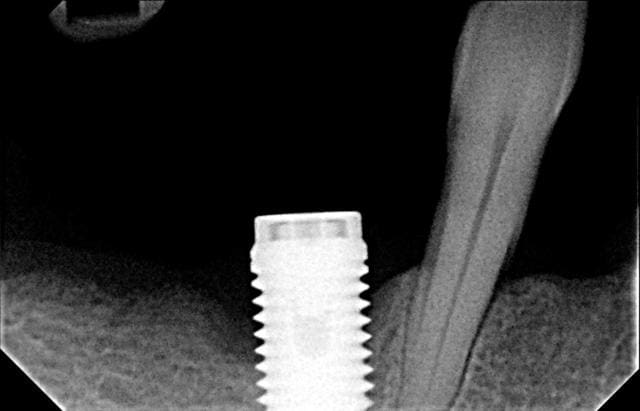

la dent, ou l'implant?

blague à part, ça semble mal barré pour l'avenir...

je vois mal cet implant servir à grand chose...

pour le tourne à gauche...pas forcément...déjà essaie avec le porte implant bien revissé et la clef à cliquet en mode dévissage...99 fois sur 100 çà suffit...